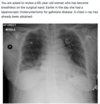

Pneumothorax Intestinal perforation resulting in pneumoperitneum **Subcutaneous emphysema** Pulmonary embolism Acute respiratory distress syndrome *You can see the striations of pec major lateral to the right lung field. Pec major is only visible if there is subcut emphysema.*